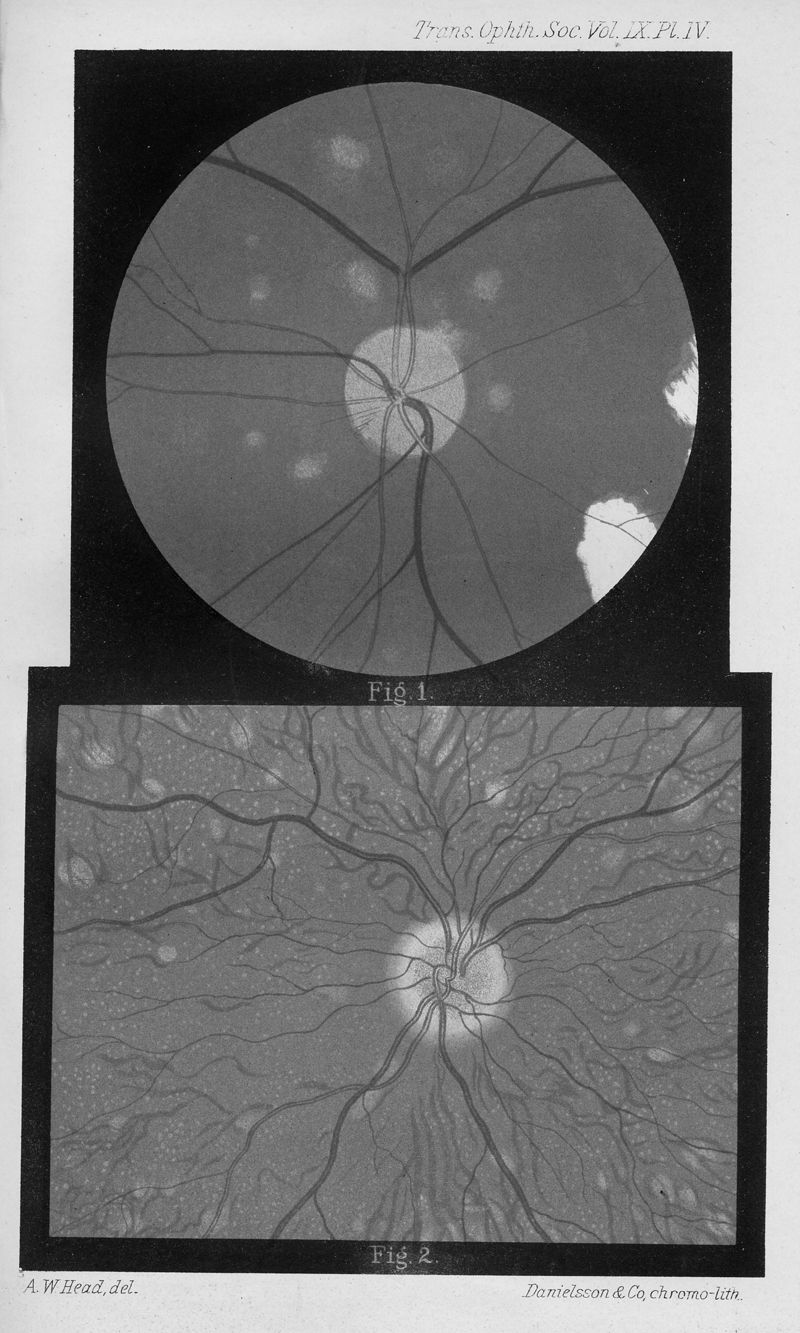

HUTCHINSON, J., Jr.

In : Transactions of the Ophthalmological Societies of the United Kingdom, 1889, Vol. 9, pp. 116-25